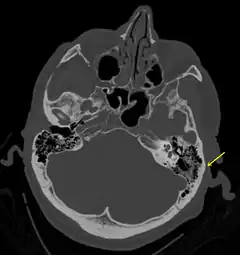

![]() Fractura del hueso temporal. | ||